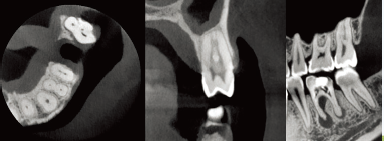

CT摄影

360°完整扫描,800帧超清影像,配合高性能CT算法,呈现细腻影像

C型臂可实现对患者头颅360°的完整扫描,最小体素尺寸0.05mm,分辨率可达2.2lp/mm,800帧超清拍摄,<60s重建时间,配合高性能算法精细重建,更适合牙体牙髓疾病的诊断。

朗视配套SmartV软件还可将采集到的数据进行多平面组合重建,不但可以同时观察到轴向面、冠状面和矢状面图像,而且可以在任意位置进行断层切面,同时获得颊舌向切片和远近中切片,方便医生诊疗。